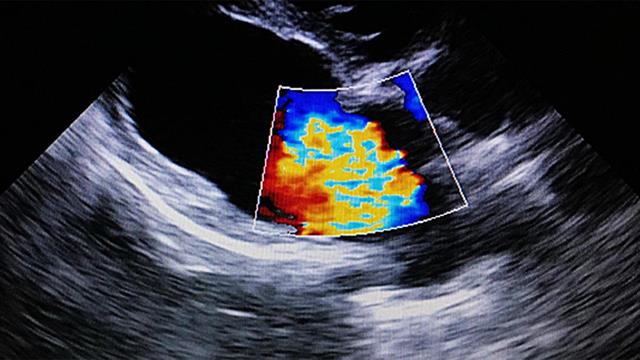

Βασικός στόχος είναι ο έγκαιρος εντοπισμός των καρδιαγγειακών παθήσεων, οι οποίες αποτελούν μια από τις κυριότερες αιτίες θανάτου, πλήττοντας συχνά ακόμα και νεότερους ανθρώπους στη χώρα μας.

"Τα καρδιαγγειακά νοσήματα αποτελούν την πρώτη αιτία θανάτου στην χώρα μας, σύμφωνα με τον Παγκόσμιο Οργανισμό Υγείας και υπολογίζεται ότι κάθε χρόνο συμβαίνουν 15-20.000 εμφράγματα, πολλά από αυτά θα μπορούσαν να έχουν προληφθεί με σωστή και έγκαιρη διάγνωση. Από σήμερα ξεκινάει το πρόγραμμα προσυμπτωματικού ελέγχου καρδιαγγειακών νοσημάτων με αποστολή μηνυμάτων sms σε 5,2 εκατομμύρια πολίτες 30-70 ετών για δωρεάν εξετάσεις για τα καρδιαγγειακά, μέσω του προγράμματος 'Προλαμβάνω' του υπουργείου Υγείας. Είναι η πρώτη φορά που η χώρα μας έχει ένα τόσο ολοκληρωμένο και συνεκτικό σχέδιο προσυμπτωματικού ελέγχου με προγράμματα και δράσεις που σώζουν ζωές καθημερινά. Το πρόγραμμα 'Σπύρος Δοξιάδης' θα μας δώσει την ευκαιρία να έχουμε μια πλήρη χαρτογράφηση των πραγματικών αναγκών και της κατάστασης της υγείας των Ελλήνων πολιτών και να σχεδιάσουμε τις πολιτικές μας για το μέλλον. Είναι σημαντικό να εξεταστεί ο πληθυσμός, διότι, με αυτόν τον τρόπο θα σώσουμε ζωές και το να σώσουμε ζωές πρέπει να είναι πάνω από την όποια πολιτική ή ιδεολογική αντιπαράθεση".